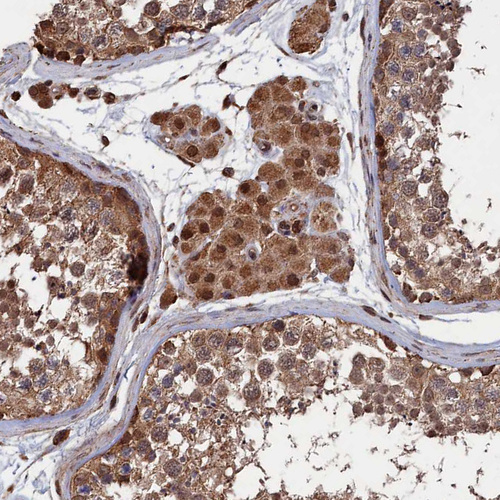

Immunohistochemical staining of human cerebral cortex shows strong cytoplasmic positivity in neurons.